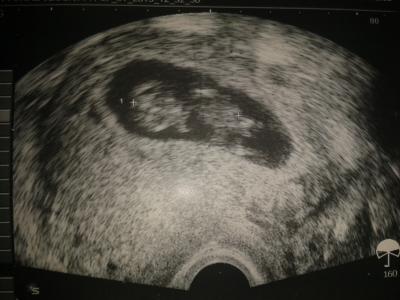

Wir sind soo zufrieden meine zyste ist noch da aber nicht so schlimm meinte der arzt.. baby ist schon weiter in der 12 woche herz hat super geschlagen... und der ET ist der 28.7 Jetzt wieder 4 wochen warten

Bild zu alles super - Forum für August - Mamis